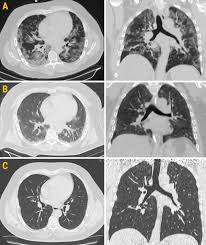

A Classification Of Pulmonary Nodules By Ct Scan Ecancer

A Classification Of Pulmonary Nodules By Ct Scan Ecancer from ecancer.org